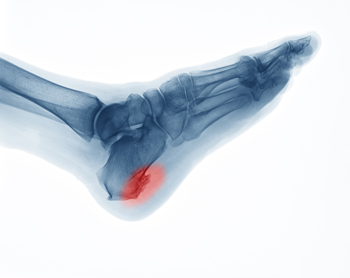

Heel spurs are the result of calcium deposits that cause bony protrusions on the underside of the heel. Heel spurs are usually painless, but they have the potential to cause heel pain. Heel spurs tend to be associated with plantar fasciitis, which is a condition that causes inflammation of the band of connective tissue that runs along the bottom of the foot. They most often occur to athletes whose sports involve a lot of running and jumping.

It is possible to have a heel spur without showing signs of any symptoms. However, if inflammation develops at the point of the spur’s formation, you may have pain while walking or running. In terms of diagnosis, sometimes all a doctor needs to know is that the patient is experiencing a sharp pain localized to the heel to diagnose a heel spur. Other times, an x-ray may be needed to confirm the presence of a heel spur.

A heel spur is a small, bony growth that develops on the bottom of the heel bone due to long-term stress on the foot. Many people with a heel spur do not need surgery, but it may be considered when pain is ongoing and limits daily movement. Heel spur surgery is usually discussed only after a podiatrist has tried other medical treatment and the pain still affects walking or standing. It may also be needed if the spur is irritating nearby tissue or causing lasting inflammation, or swelling and pain in the area. A podiatrist can examine the foot and review imaging like X-rays to determine if surgery is needed. The procedure can remove the spur and reduce strain on the surrounding structures to improve comfort and function. If you have pain from a heel spur, it is suggested that you make an appointment with a podiatrist to see if surgery is an option.